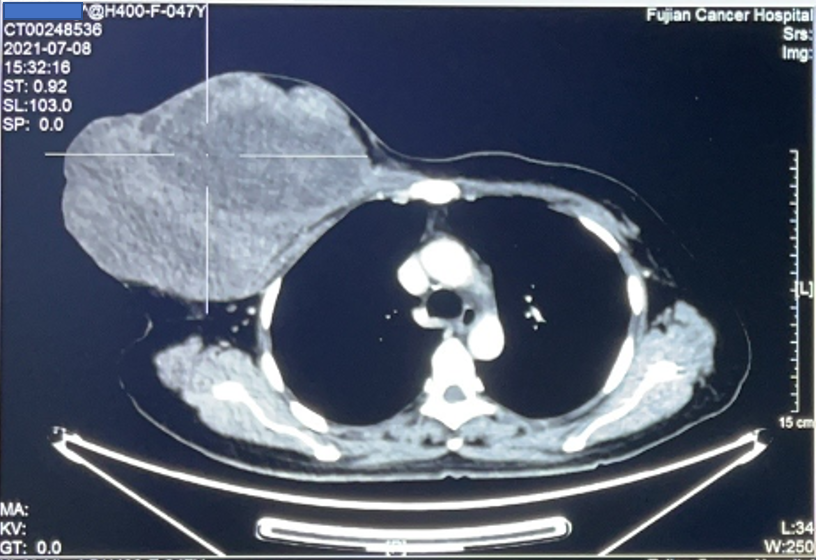

患者为47岁女性,发现右乳腺肿块半年,半年前肿块约网球大小,后逐渐生长增大到约25*22cm大小,伴有肿块的破溃、渗血、恶臭。患者深受困扰,痛苦不堪,辗转省内多家医院就诊,均被告知手术难度大、风险高。最后求诊我院,接诊患者后,乳腺肿瘤外科叶文飞主任组织团队成员游原瑜、黄志坚、黄秋艳、陈建医师、麻醉医师及护理团队,进行病情讨论和手术方案的制定。

胸壁恶性肿瘤常累及皮肤,胸大肌,深达肋骨表面,为减少复发需行肿瘤扩大切除,常造成胸壁巨大缺损。此类患者术后多需放化疗,为争取时间,采取快速可靠方法修复创面缺损具有重要意义。叶文飞主任考虑该患者创面巨大,不能直接缝合,需要进行肌皮瓣转移修复胸壁缺损。传统的背阔肌皮瓣因背部皮肤弹性较差,宽度一般不超过8 cm,否则供区不能直接拉拢缝合,甚至需植皮修复。因此巧妙设计,采用一蒂双瓣方式,设计背阔肌Kiss 皮瓣,两瓣对缝修复巨大创面,缩小了供区缺损,避免了植皮导致的一系列并发症。